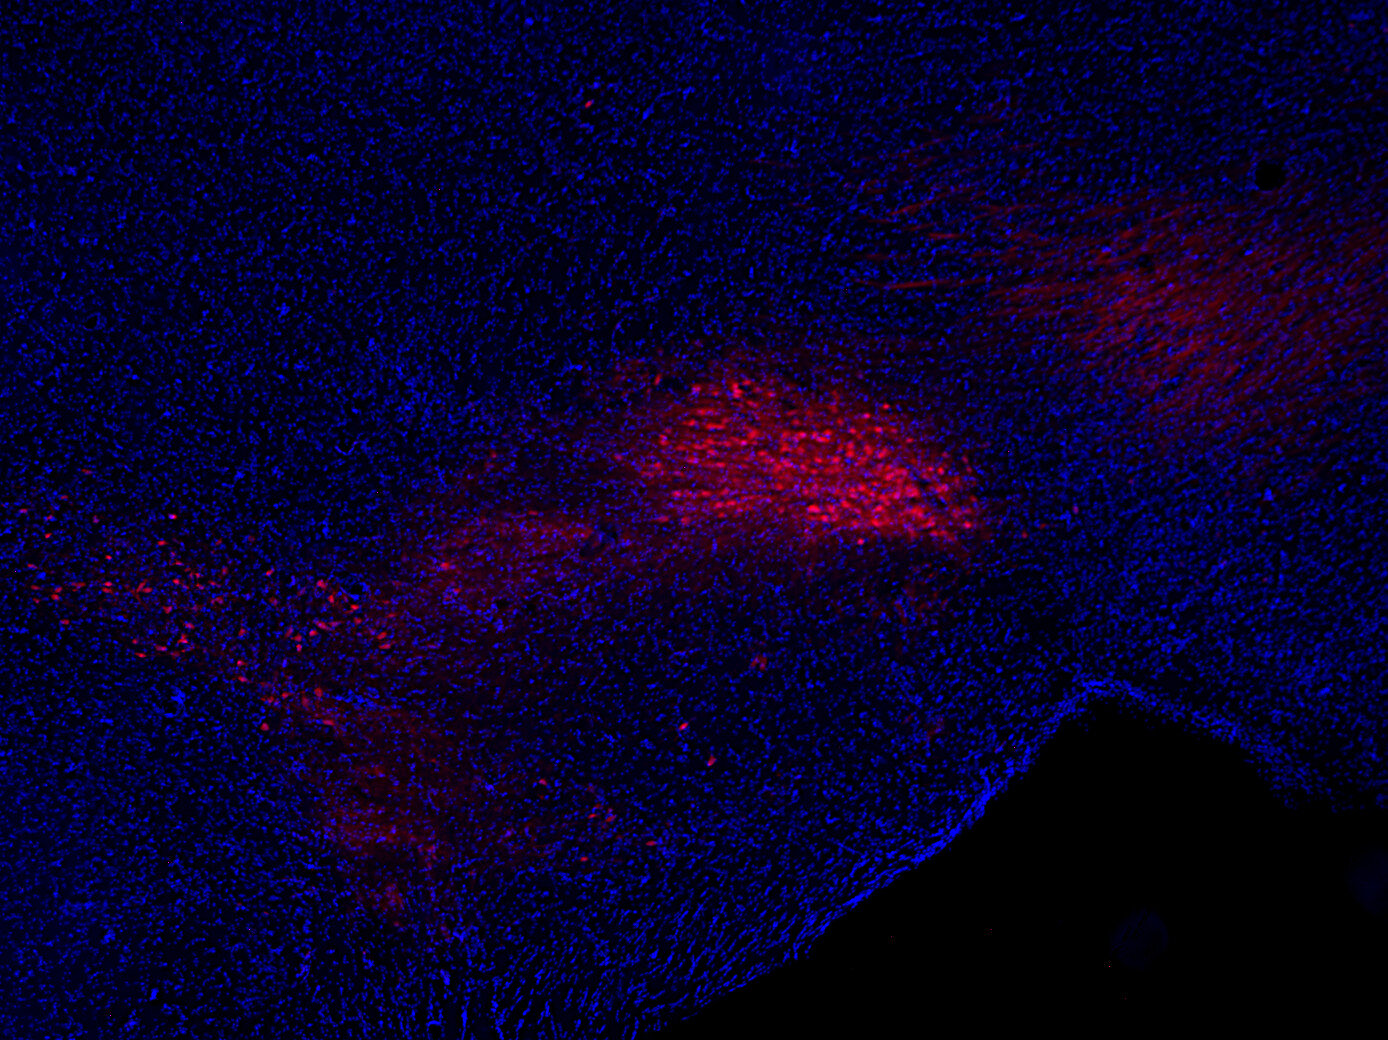

IHC: 1 : 500 up to 1 : 5000 gallery

Immunohistochemistry (IHC) on 4% PFA perfusion fixed tissue with 24h PFA post fixation. Immunoreactivity is usually revealed by fluorescence or a chromogenic substrate. Some antibodies require special fixation methods or antigen retrieval steps. For details, please refer to the ”Remarks” section.